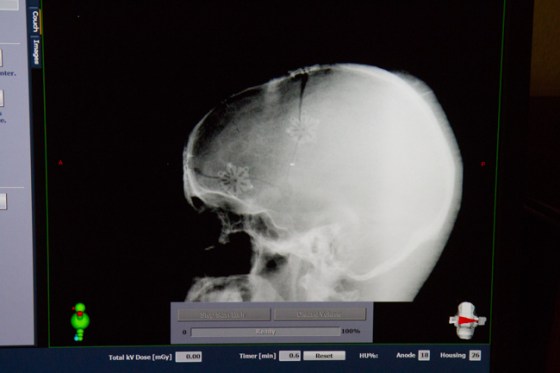

He has a skull held together with snowflakes protecting his brain.

Yes this is the cranium of Rockin’ Roy other wise known as Roy Alan Danehy

Diagnosed last October with Glioblastoma Multiforme Grade IV

Not a good type of brain cancer to get.

Luckily for Roy’s cancer they said something could be done.

I am scared looking at these images.

I see the tumor coming back even though I’m not sure what I’m looking at.